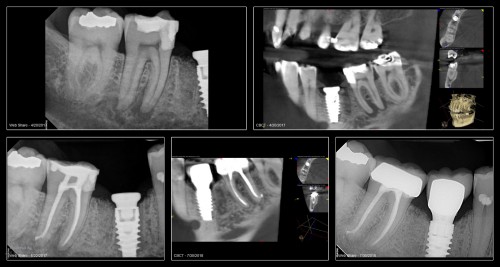

Dynamically Guided Endodontic Access

Dynamic navigation has been in dentistry for many years. It remains in its infancy in […]